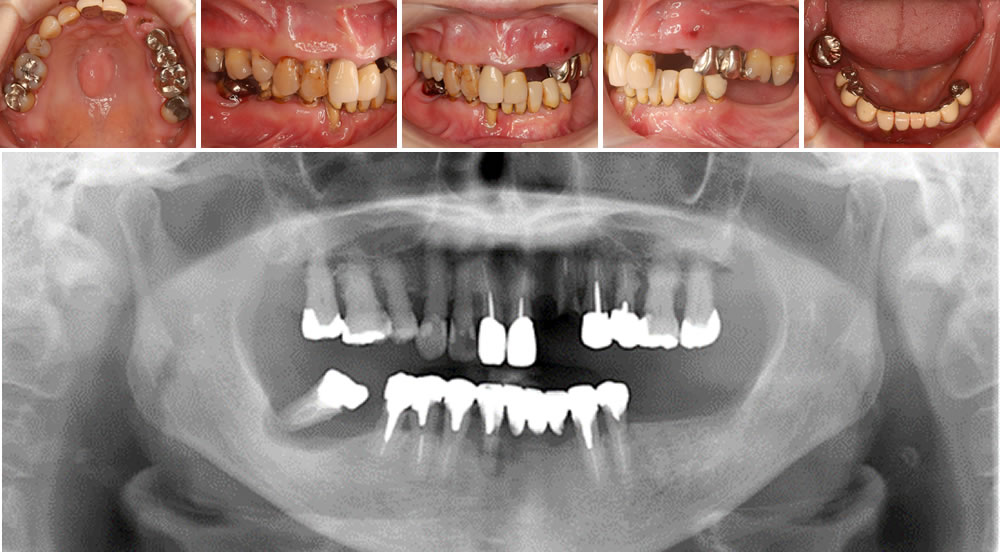

自費のコーヌスデンチャーで噛み合わせを回復した症例

こちらの患者さまは、「前歯がないから入れたい」「歯茎が腫れてくるのでなんとかして欲しい」「しっかり噛めない」との主訴で来院されました。

口腔内診査を行うと、歯周病も進行して奥歯がぐらぐらしていました。レントゲン検査の結果、上は右上1~3番、左上1番以外を抜歯、下は右下3~5番、左下3・4番以外は抜歯と診断しました。患者さまと相談し、インプラントはしたくないがしっかり治したい・噛みたいとのことでしたのでコーヌス冠を使った自費の入れ歯を製作することにしました。

完成した自費のコーヌスデンチャーです。コーヌスデンチャーは、残存歯に装着した内冠と入れ歯側の外冠を茶筒の原理で固定するため、安定性が高く、しっかり噛むことができます。

完成したコーヌスデンチャーをお口に装着し、治療完了です。咬合も安定しており、経過も順調です。

| 年齢・性別 | 60代 女性 |

|---|---|

| 治療期間 | 6ヵ月 |

| 治療回数 | 15回 |

| 治療費 | 上顎 コーヌスデンチャー 440,000円(税込) 下顎 コーヌスデンチャー 920,000円(税込) |

| リスク・注意点 | ・歯がダメになったら修理しないといけない |